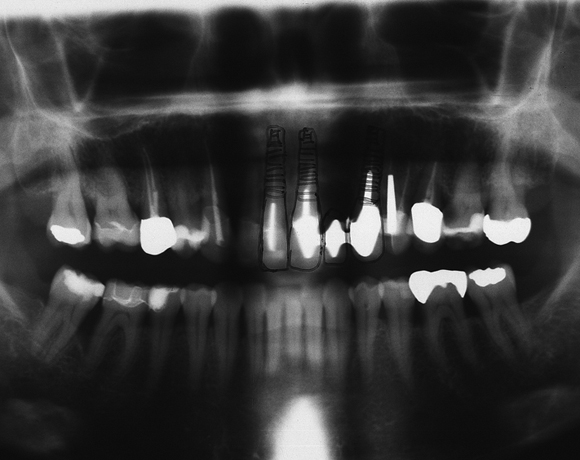

Drei Implantate in der Oberkieferfront

Ein Projekt aus dem Jahr 2011

Im vorliegenden Patientenfall mussten die 11 bis 22 aus parodontalen Gründen extrahiert werden. Die Zähne hatten Lockerungsgrad III, und es bestand ein starker horizontaler Knochenabbau. Das Ergebnis zeigt die Abschlusssituation nach Knochenaufbau und der Insertion von drei Vollkeramikimplantaten.